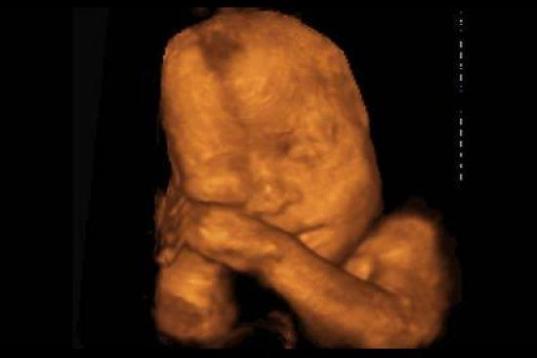

En esta galería puedes ver en fotos como es el desarrollo de un feto de semana en semana:

Desarrollo del feto, en fotos